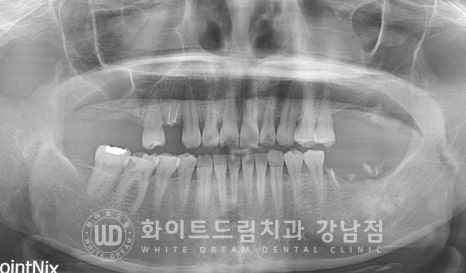

환자분의 초진 구내 상태입니다.

16,17번 치아는 상실된 상태이고

14, 27, 36,37번 치아가 뿌리만 남아있는 상태입니다.

뿌리만 남아있는 치아들은 모두 신경치료를 받은 흔적이 보이는데

신경치료 후 크라운을 씌우지 않으셨고,

있던 크라운도 시간이 지나면서 탈락된 상태로 방치를 하셔서

치아가 모두 저작력을 버티지 못하고 부러져버린 상태인 것이죠.